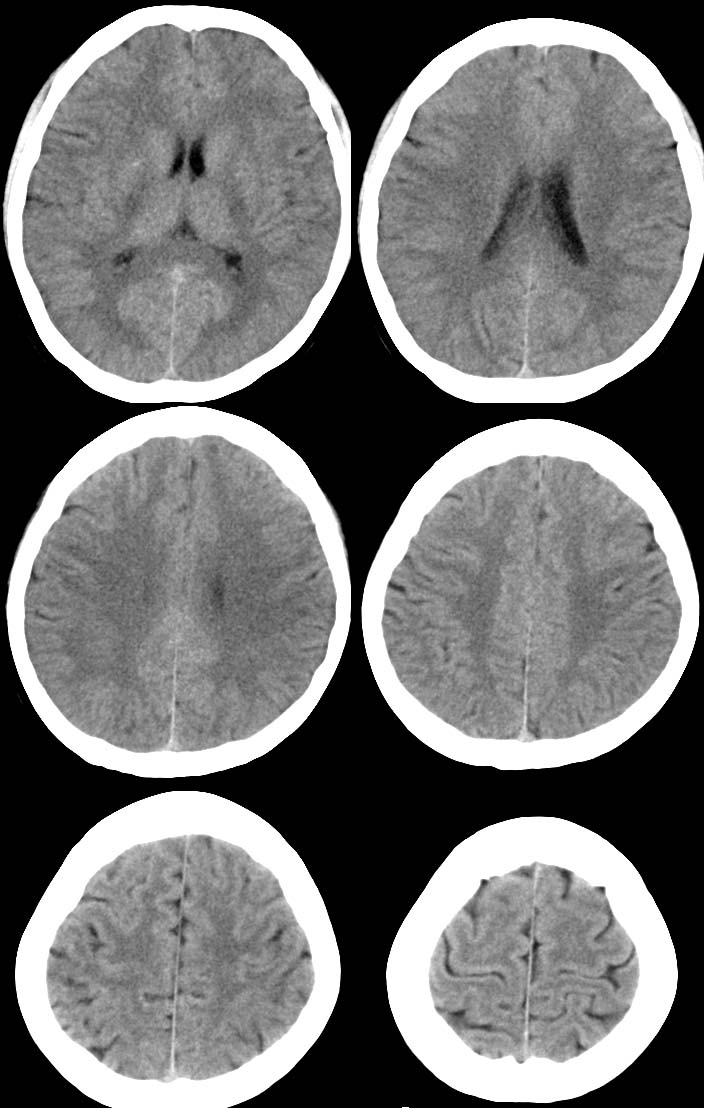

病人女 35岁 自述头晕 头痛

双侧基底节区及右侧丘脑区多发点状钙化,周围未见水肿及占位征象.余未见明显异常.考虑:脑囊虫病<囊虫的退变或死亡期>请结合有无相关病史.

以下是引用苯小孩在2007-4-20 15:47:00的发言:[br]双侧基底节区及右侧丘脑区多发点状钙化,周围未见水肿及占位征象.余未见明显异常.考虑:脑囊虫病<囊虫的退变或死亡期>请结合有无相关病史.

颅内有散在钙化

脑囊虫病理性钙化。